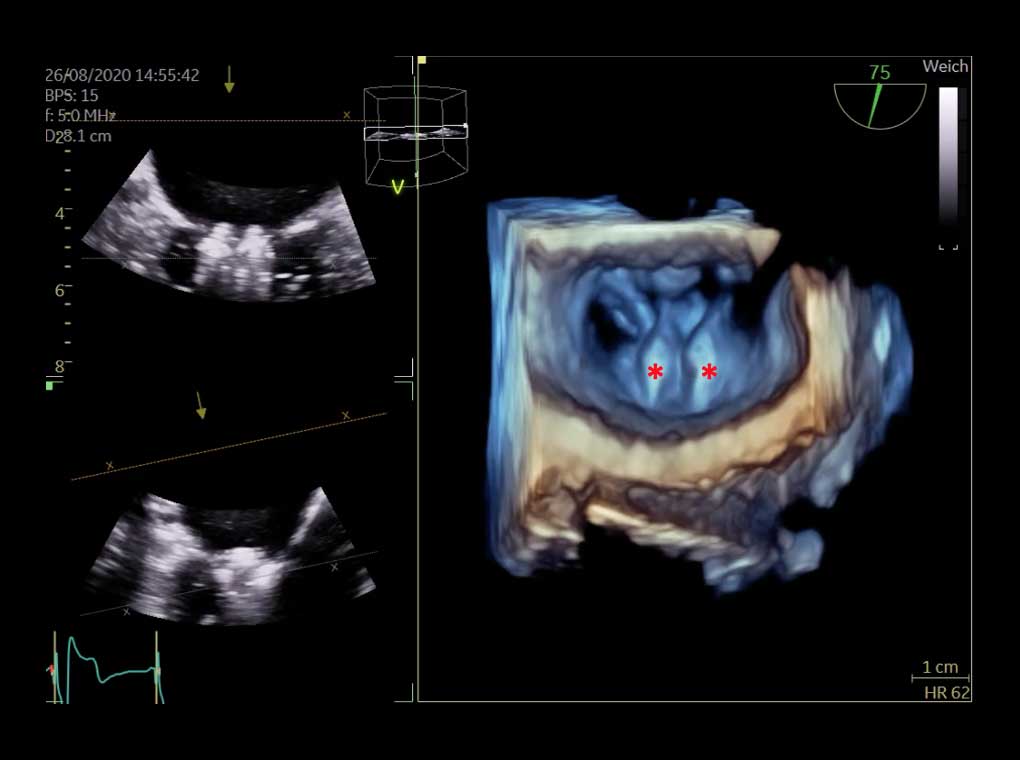

3D-TEE bei Kathetergestützter Mitralklappenrekonstruktion mit PASCAL-System

Ausrichten  —>

Greifen —>

Schließen —>

Ablösen

Behandlung der Mitralklappe:Kathetergestützter Mitralklappenrekonstruktion mit PASCAL-System

Annäherung beider Segel mit 2 PASCAL Implantaten (*)

Reduktion der Mitralklappeninsuffizienz auf Grad 1

3D-TEE Untersuchung der Mitralklappe vor und nach dem PASCAL Eingriff

Reduktion der Mitralinsuffizienz von Grad 3 auf Grad 1